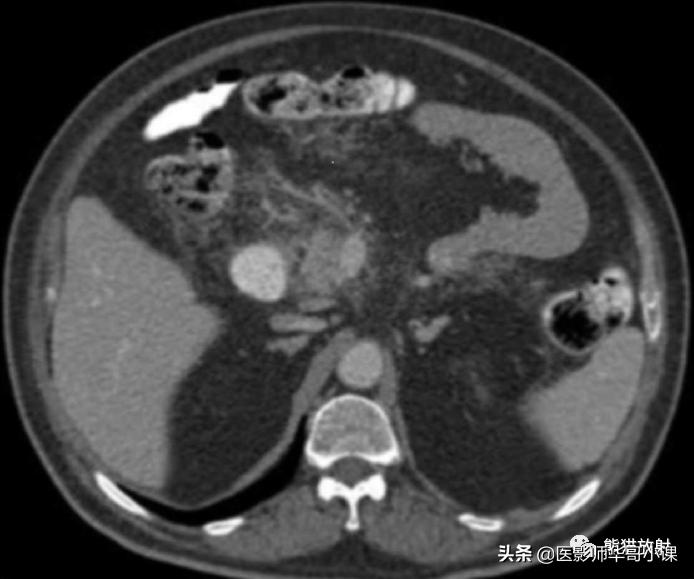

5、急性胰腺炎 Acute Pancreatitis

急性胰腺炎时,外渗的胰酶沿肠系膜解剖路径扩散。 胰外急性积液可以沿横结肠系膜根部蔓延 ,有时,也可沿小肠系膜根部蔓延,以及沿血管扩散至横结肠和小肠的直小血管(图)。

急性胰腺炎扩散。增强CT显示炎症从横结肠系膜向横结肠扩散